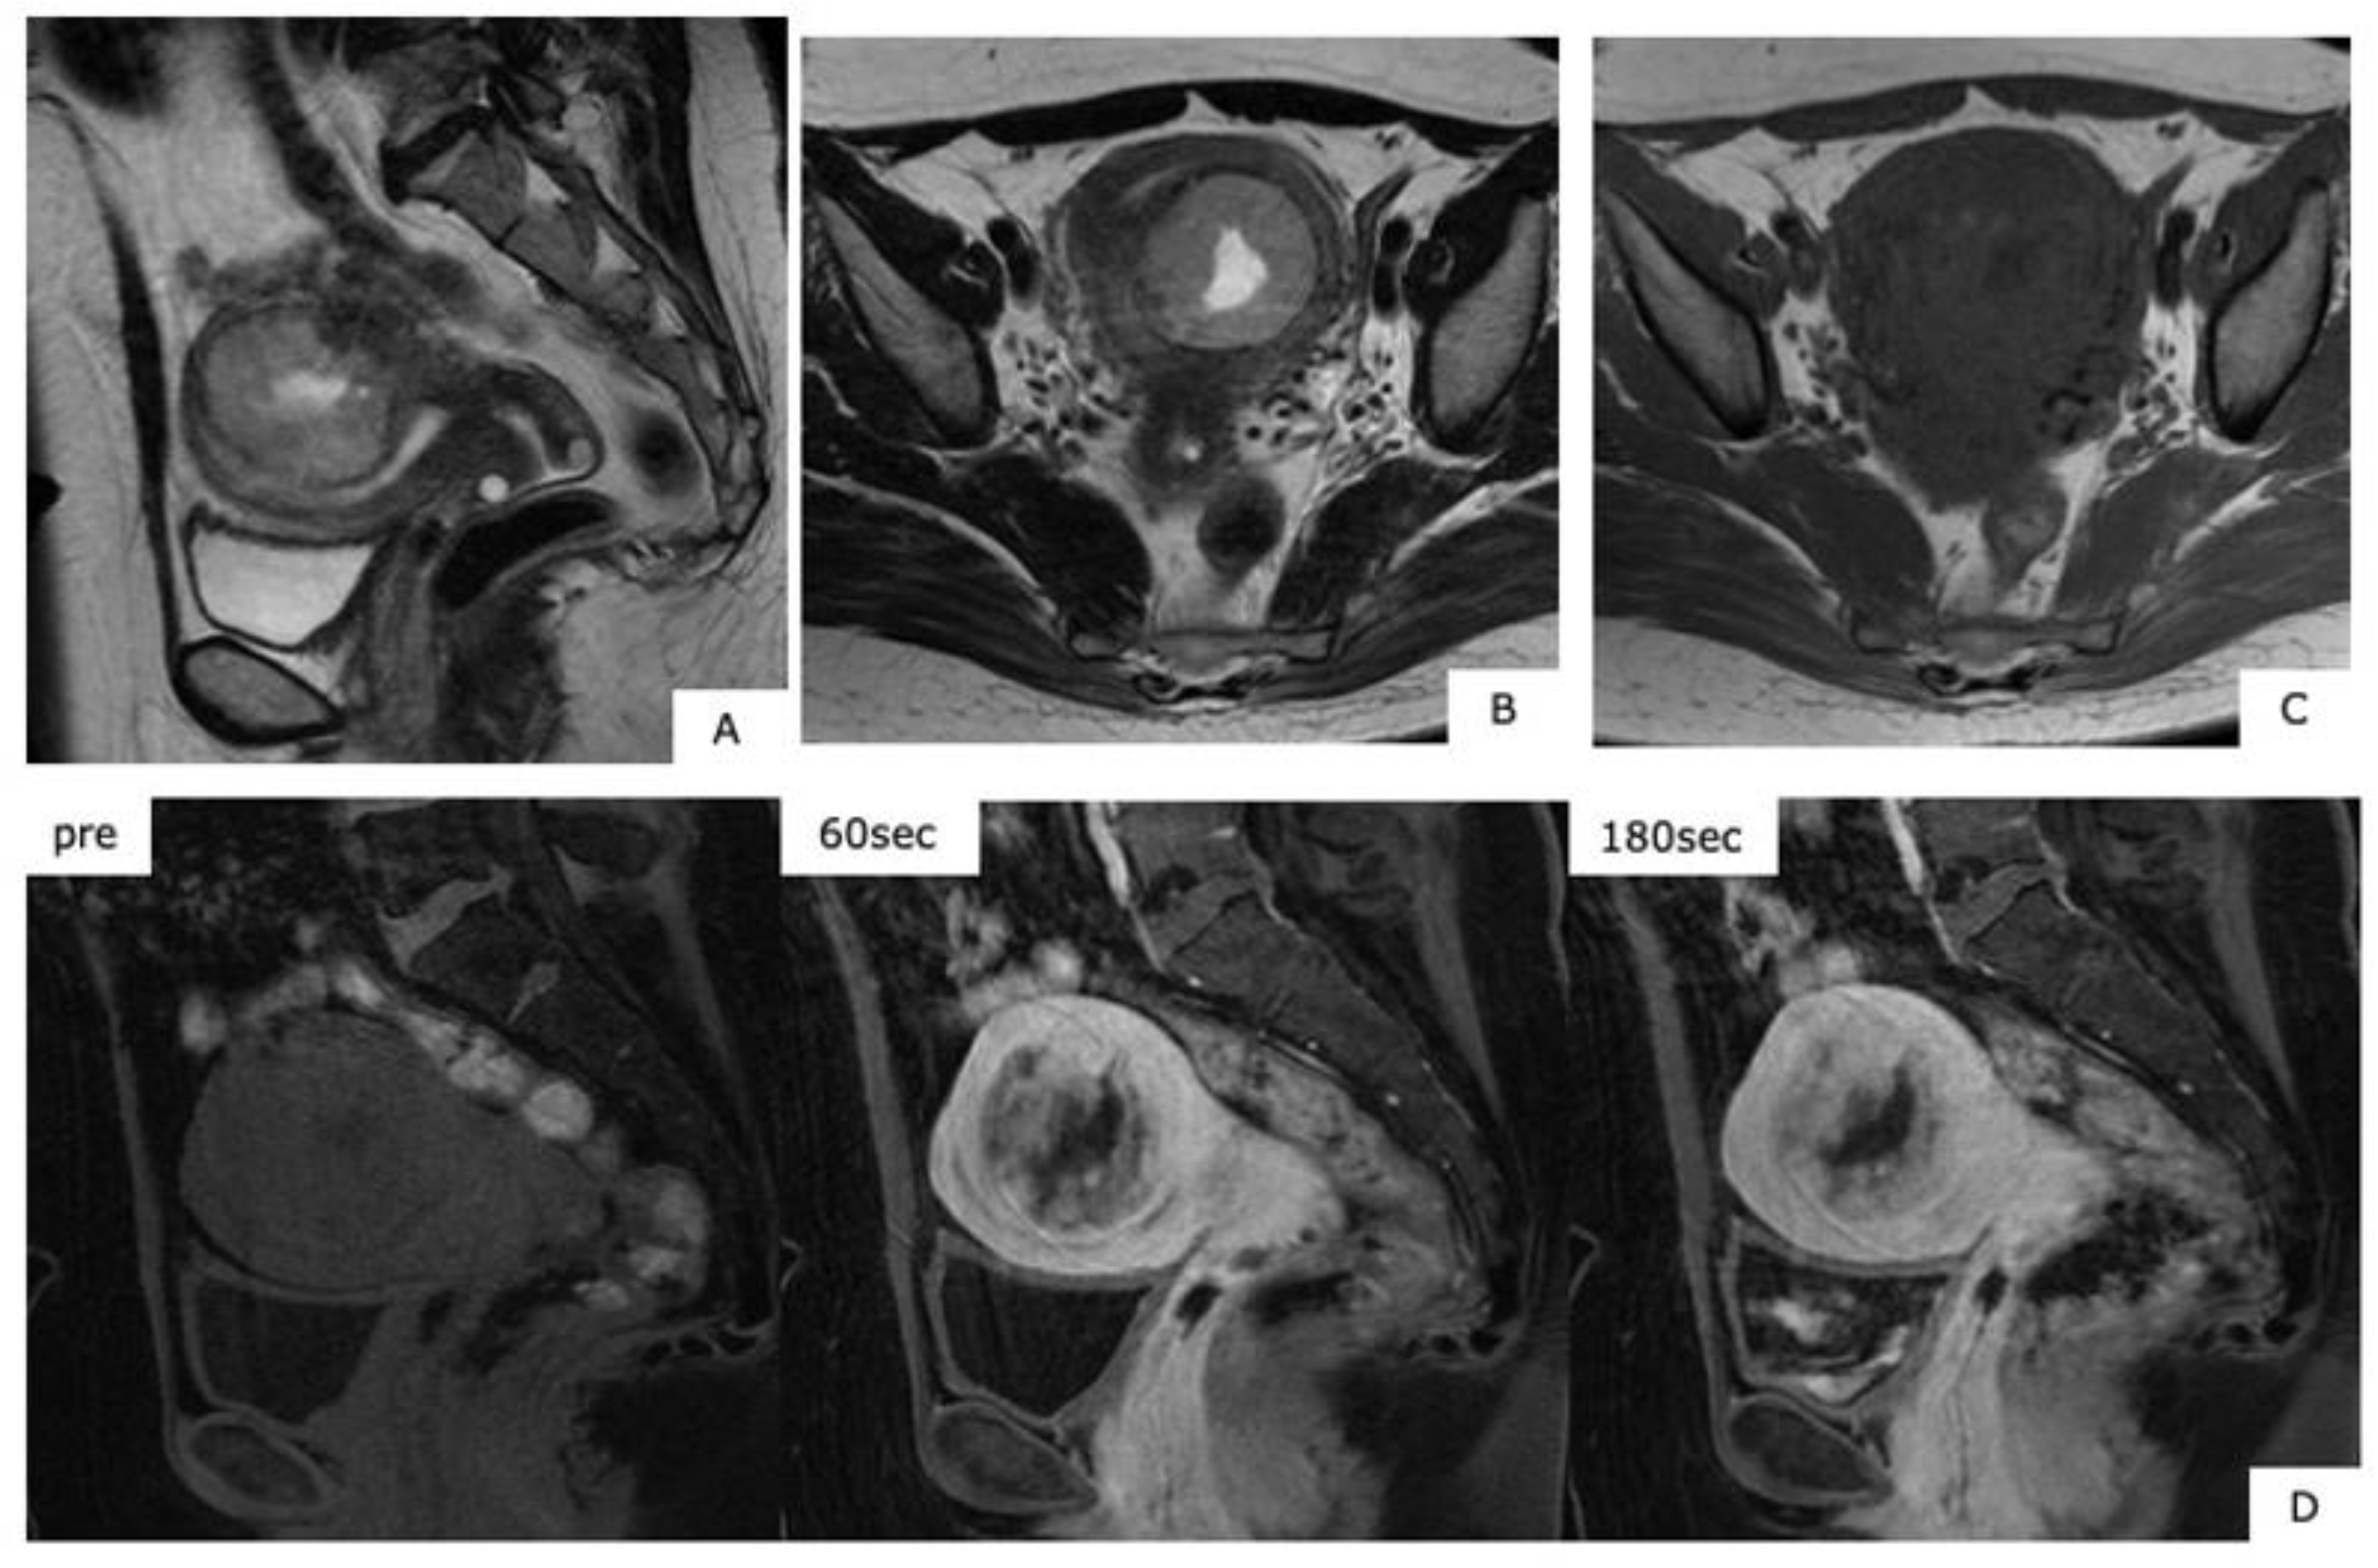

A Figure 2 Mri Of The Pelvis In A 70 Year Old Patient With Grade 3 Download Scientific Diagram